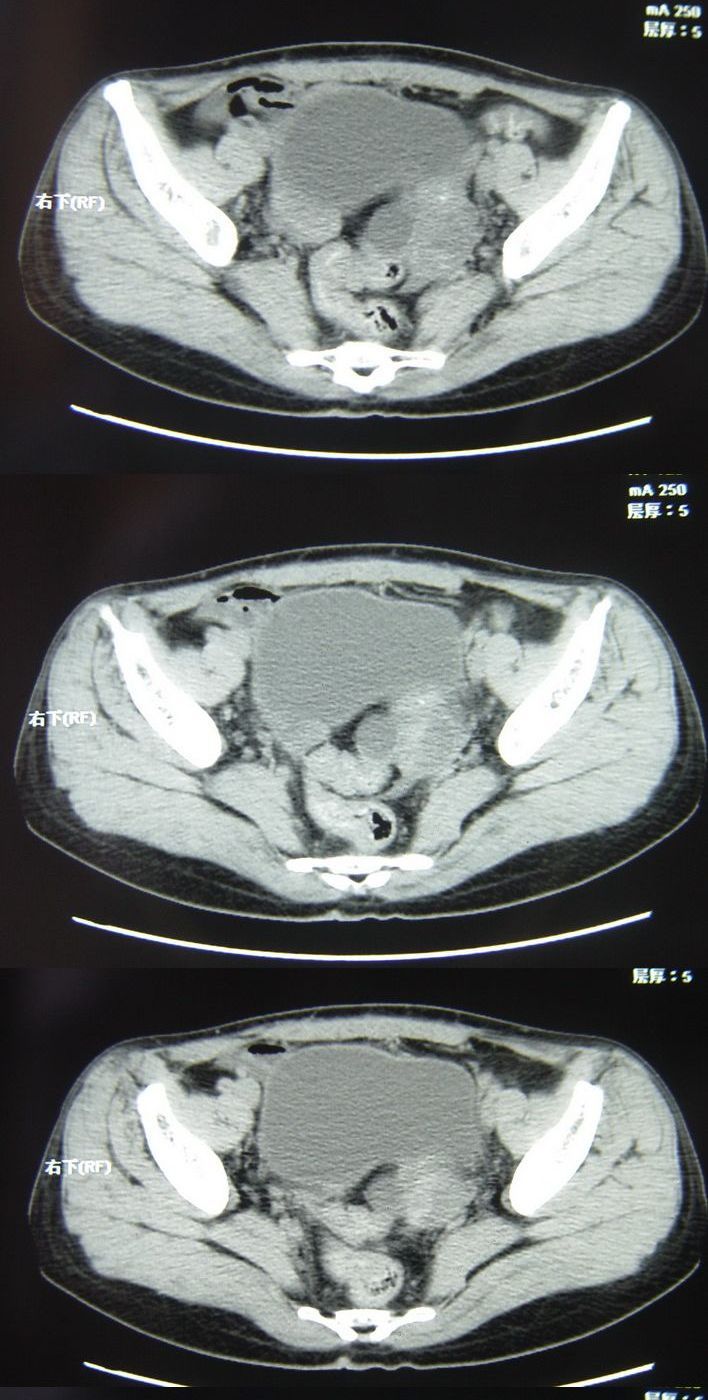

以下是今天的增强片,大家可以看看:

该病人今天做了增强,右侧髂骨病灶明显强化。

临床和影像学表现:女性患者46岁,有子宫肌瘤手术病史。影像所见可见残余宫颈部分,左右附件未见新生物;右髂骨翼后端囊状膨胀性骨破坏,囊性部分感觉有强化(楼主标上增强前后的ct值就很好了),未见明确的液—液平面,周边硬化不明显或轻度硬化。

分析:患者年龄46岁,没有明确外伤病史,病变呈膨胀性骨破坏,囊性部分未见明确的液—液平面,周边硬化不明显。综合分析该病例比较符合骨巨细胞瘤,不太符合动脉瘤样骨囊肿。

诊断:1、首先考虑骨巨细胞瘤;2子宫肌瘤术后改变